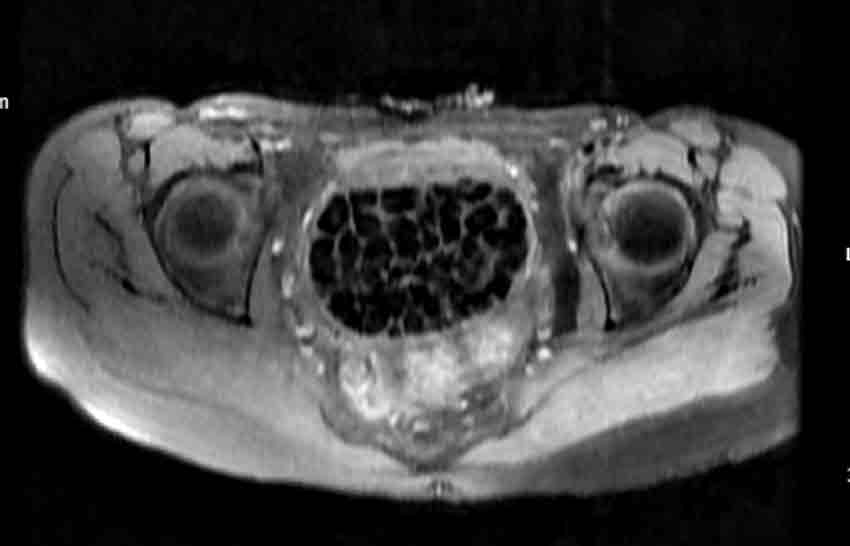

Hastasının durumuna yönelik konuşan Üroloji Uzmanı Doç. Dr. Erkan Erkan, "Hastamızın 2004 yılında doğduğunu ardından doğar doğmaz ekstrofi vezika dediğimiz 50 binde bir görülen bir anomaliden dolayı art arda ameliyatlar geçirdiğini öğrendik. 10 yaşında yine bir ameliyat geçirmişti, gerekli görüntüleme ve tetkiklerimizi yaptırdık. Normalde mesanesinin olması gereken yerin hemen arka kısmında taşlarla dolu bir kese olduğunu gördük, bunun üzerine ek görüntülemeler; MR çektirdik. Hastamız çelişkili açıklamalar almıştı, kendi radyolojik kliniğimiz ve edindiğimiz konsültasyonlarda taşların mesanede değil vajinal boşlukta oluştuğunu düşündük, bir planlama yaptık. Kadın doğum hocamızın da çabasıyla taşları tamamen temizledik ardından ileride normal bir hayat sürmesi bakımından oraya plastik cerrahi yaptık. 287 adet taş çıkardık, pratikte gerçekten görünce çok şaşırdık çünkü bu aynı zamanda literatürde çok nadir görülen bir olay. Biz ameliyata hazırlanırken de teorik olarak biraz araştırdık. Literatürde gördüğümüz kadarıyla buna benzer bu tanıma uyan bir vaka vardı. Literatürde sanırım yayınlanmış 2’nci vaka olacak. Farkındalık çok önemli, bilinçli bir hastamız vardı. Doğumsal anomaliyle doğan çocuklarımızda ileride bunlara bağlı bazı sıkıntılar çıkabileceğinin öngörülmesi lazım. İlgili tedavilerini alsalar bile düzenli takiplere gelmeleri gerekiyor. İleride eğer dikkat etmezse ki zannetmiyorum, tekrarlayabilir. Bu rahatsızlık ekstrofi vezikal epispadias durumu çok nadir bir durum" dedi.

Genç kızın uzun süredir devam eden karın ağrısı olduğunu söyleyerek sözlerine başlayan Jinekolojik Onkoloji Uzmanı Op. Dr. Emin Erhan Dönmez, "Mesane taşları olduğu düşünülerek daha büyük bir hastaneye refere edilmiş. Aramızda mini bir konsey yaparak muayene ettik. Vajen bir hazne görevi görerek orada durağan bir idrar, uzun süre beklediği için idrar içindeki minerallerde çökerek taşlar oluşmuş. Mesanedeki idrarın vajene akmış olabileceği ve vajende göllenen idrar nedeniyle taşların burada oluşacağını düşündük, ameliyatımızı planladık. Ameliyata tanı amaçlı girmiştik, sistoskopi (Mesane gibi idrar yollarını kapsayan kısımlardaki rahatsızlıkların teşhis ve tedavisinde kullanılan endoskopik bir yöntem) dediğimiz ameliyatı Erkan Hocam ile birlikte gerçekleştirdik. Önce mesaneyi bir görüntüledik, mesane tabanına yaklaşık 2-3 cm’lik bir alandan vajene fistülize olduğunu gördük. Mesaneden vajene geçtiğimiz esnada tüm vajenin taşlarla dolu olduğunu gördük. Tanı amacıyla girdiğimiz ameliyatta her şey de olağan gittiği için tedaviye geçtik. Taşların çıkabileceği kadar bir genişlik sağladık. Daha sonra yaklaşık en büyüğü 2,5 cm boyutlarında olan, irili ufaklı 287 tane taşı ameliyat esnasında çıkarmış olduk. Taşların tekrarlamaması için idrarın göllenmemesi, en azından dışarıya rahatça boşalabilmesi için vajinal rekonstrüksiyonu sağladık. Ameliyatta da herhangi bir problem yaşamadık. Literatürü Erkan Hocam ile birlikte değerlendirmiştik. Primer olarak vajende birikmiş olan bu kadar çok sayıda taşla ilgili bir makale görmedik, rastlamadık" dedi.